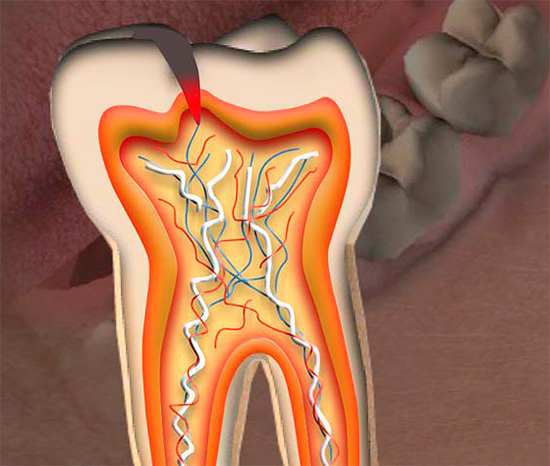

Nella fase terminale, la lesione raggiunge la polpa. In questo caso, i dolori acquisiscono un carattere completamente diverso: anche dopo l'eliminazione dell'irritante, durano a lungo, compaiono dolori spontanei (senza motivo apparente), notte, irradiamento o tiro (cedendo in qualsiasi zona della regione maxillo-facciale), dolore lungo, palpitante, lacrimante, intollerabile e t. d.

Tutte queste sono complicazioni della carie, chiamate pulpite o parodontite, a seconda dello stadio di danno al "nervo" nei canali del dente. In questa fase, il paziente è costretto a consultare un medico per le cure di emergenza e il trattamento viene eseguito secondo la diagnosi. È caratterizzato da manipolazioni tecnicamente più complesse rispetto al trattamento della carie e passa più spesso attraverso diverse fasi importanti prima del riempimento stesso. In termini di tempo e componente finanziario, questa è un'impresa costosa.